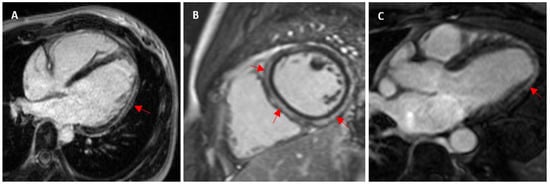

- Cummings, K.W.; Bhalla, S.; Javidan-Nejad, C.; Bierhals, A.J.; Gutierrez, F.R.; Woodard, P.K. A pattern-based approach to assessment of delayed enhancement in nonischemic cardiomyopathy at MR imaging. Radiographics 2009, 29, 89–103. [Google Scholar] [CrossRef] [PubMed]

- Wilson, M.; O’Hanlon, R.; Prasad, S.; Deighan, A.; MacMillan, P.; Oxborough, D.; Godfrey, R.; Smith, G.; Maceira, A.; Sharma, S.; et al. Diverse patterns of myocardial fibrosis in lifelong, veteran endurance athletes. J. Appl. Physiol. 2011, 110, 1622–1626. [Google Scholar] [CrossRef]

| Wilson et al. (2011) [20] 1.5 T | 29 12 lifelong veteran endurance and 17 young endurance: marathon, ultramarathon, ironman, triathlon | Veteran: 43 ± 6 y of competitive training Young: 18 ± 7 y of competitive training | 57 ± 6 31 ± 5 | M: 100 1.96 ± 0.14 2 ± 0.14 | Veteran: 6/12 (50%) Young: 0/17 Total: 6/29 (20.7%) | 1 CAD pattern: subendocardial septal and lateral wall infarction pattern 5 non-CAD pattern: 1 subepicardial lateral wall (myocarditis), 4 junctional: basal and mid insertion point, inferior insertion point and mid/apical, inferior mid/apical insertion point, inferior insertion point | - | - |

| Breuckmann et al. (2009) [24] 1.5 T | 102 Marathon runners | ≥5 marathons in ≤3 y | 57 ± 6 | M: 100 | 12/102 (11.8%) | 5: subendocardial layer typical myocardial infarction (10 LAD, 1 LCA, 3 RCA segments) 7: mid-myocardial patchy nonischaemic pattern (3 LAD, 5 LCA, 9 RCA segments) | - | - |

| Tahir et al. (2018) [11] 1.5 T | 83 Triathletes | 12.6 y competitions, >10 h/wk training | 43 ± 10 | M: 65 1.98 ± 0.12 F: 35 1.73 ± 0.12 | M: 9/54 (16.7%) F: 0/29 Total: 9/83 (10.8%) | Nonischaemic: 5: subepicardial (myocarditis)–inferolateral LV wall, 2: posterior RV insertion points, 1: transmural | M: 990 ± 28 F: 1015 ± 25 M: LGE+ 1005 ± 32 M: LGE- 987 ± 27 | M: 24.8 ± 2.2 F: 27.8 ± 1.9 M: LGE+ 26.3 ± 1.8 M: LGE- 24.4 ± 2.2 |